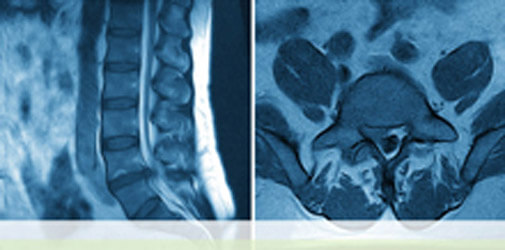

Insgesamt handelt es sich bei den nunmehr fünf verschiedenen Methoden der minimal-invasiven Bandscheibenverfahren um Eingriffe, die unter Schonung des Rückenmarkskanals durch eine entsprechend durchgeführte Tunneltechnik von außen in das Bandscheibenfach gelangt. Wichtig ist hierbei im operativen Vorfeld eine genaue Diagnostik mittels Kernspintomographie (MRT) und entsprechenden Druckstimulationen der Bandscheibenetagen (Diskographie) durchzuführen, um die Diagnose hundertprozentig zu sichern. Es ist absolut unabdingbar, die klinische Situation mit der entsprechenden Schmerzsymptomatik und Schmerzausstrahlung im Bezug auf die durchgeführte Diagnostik abzustimmen.

Bei der „schwarzen Bandscheibe“ ist eine richtige Vorwölbung nicht vorhanden, man kann jedoch auf der MRT-Aufnahme eine deutliche Signalabschwächung der betroffenen Bandscheibe dokumentieren. Diese „diskogenen Schmerzen“ werden durch eine Rissbildung des hinteren Bandscheibenfaches verursacht, da es hier über einen kurzen Zeitraum zu einer deutlichen Einsprießung von Schmerzfasern kommt.

Bilder zu Minimal-invasive Schmerztherapie